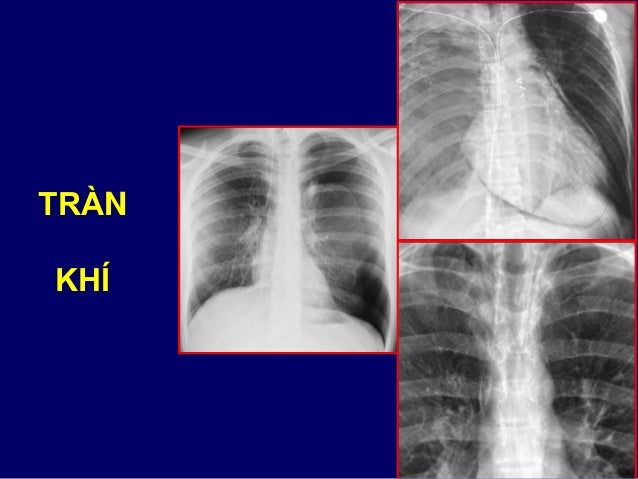

27. 27. Profil droit Petite scissure Grande scissure LSD LM LID

28. 28. Scissure gauche LSG Lingula = LM LIG Culmen = LSD Profil gauche

29. 29. TIỂU THÙY PHỔI

30. 30. TIỂU THÙY PHỔI

50. 50. TRÀN KHÍ

51. 51. TKMP (T) ÁP LỰC

53. 53. THÔNG ĐIỆP CẦN NHỚ VỀ TỔN THƯƠNG TRÀN KHÍ  Tìm dấu mất nhu mô + lá tạng màng phổi  Tìm có dấu TKMP áp lực  Phim XQ thì thở ra giúp thấy rõ TKMP nhỏ  Cần phân biệt với nếp gấp da, bóng khí  Hễ thấy gãy xương sườn thì tìm TKMP  TKMP lượng lớn có thể  tăng tưới máu phổi còn lại